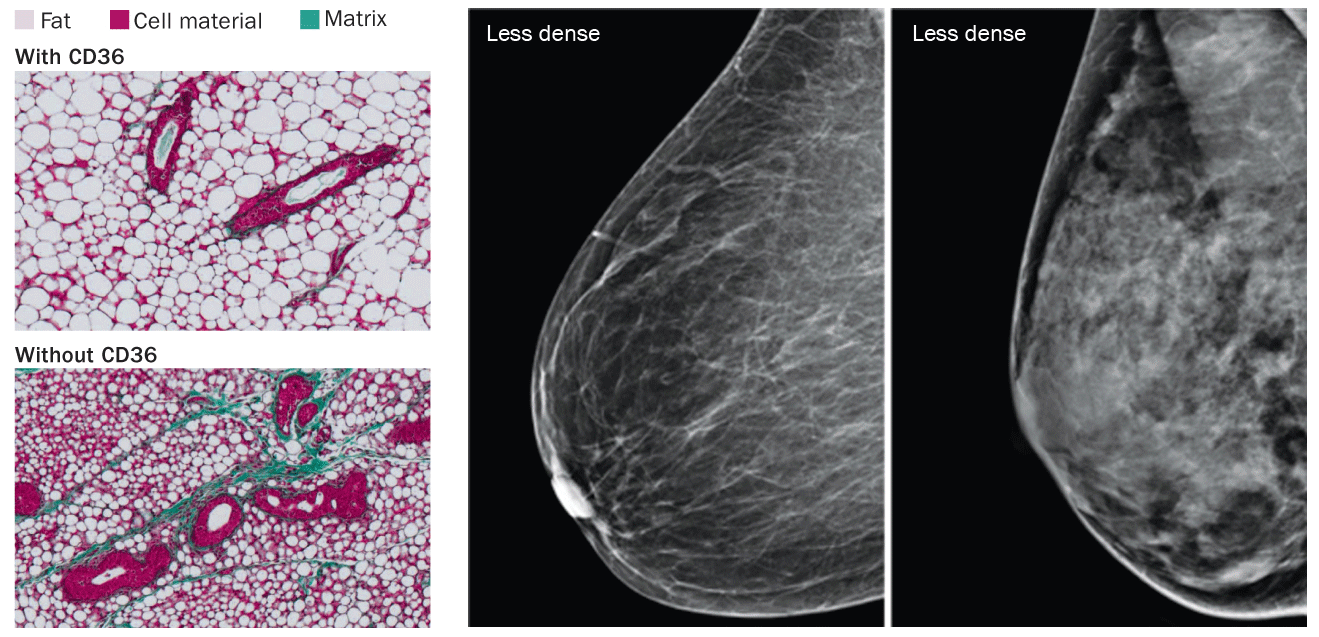

Delicate strands of extracellular matrix proteins such as collagen and elastin are barely visible on mammograms of healthy breasts, says Thea Tlsty, a molecular pathologist at the University of California, San Francisco.

But in some women’s breasts, collagen, elastin and other extracellular matrix proteins form thick ropes of connective tissue that appear as stringy white material on a mammogram. Those women are said to have dense breasts and are at increased risk of developing breast cancer.

Tlsty and her colleagues discovered that a protein that helps strike a balance between making fat and producing connective tissue is partly responsible. The protein, called CD36, exists on many types of cells. CD36 is a busy molecule, regularly making contact with a wide variety of proteins in the extracellular matrix and on neighboring cells. Among its many roles, CD36 controls processes that can promote healthy breast tissue. When missing, it leaves behind an environment that allows cancer to grow, Tlsty and her colleagues reported last year in Cancer Discovery.

Rosa Anna DeFilippis from Tlsty’s team studied breast tissue fibroblasts from women who had undergone breast reduction surgery or who had had tumors removed. Fibroblasts are cells that help construct connective tissue, and are some of the main builders of the extracellular matrix components that contribute to breast density.

Women with low breast density (more fat than connective tissue) had more CD36 on their fibroblasts than women with high breast density. Fibroblasts with low levels of CD36 pump out more of the stuff, like collagen, that creates the whiteness on mammograms, Tlsty says. Lower levels of the protein also spark other cancer-stimulating changes. Immune cells that don’t make CD36 transform from tumor fighters into cancer promoters. And wiping out CD36 from blood vessel cells removes the brakes that normally keep vessel growth in check, the researchers found.

Tlsty’s group has seen these procancer changes in the stroma occur before there’s a tumor. “That’s amazing,” she says. It suggests that the stroma goads tumor growth. Everybody else thought that the tumor itself caused the abnormal growth of connective tissue, she says. Perhaps correcting the CD36 levels could eventually be both therapy and prevention for breast cancer, she says.